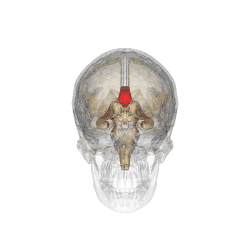

![]() Corpus callosum from above, front part at the top of the image | |

The corpus callosum (Latin for "tough body"), also callosal commissure, is a wide, thick nerve tract, consisting of a flat bundle of commissural fibers, beneath the cerebral cortex in the brain. The corpus callosum is only found in placental mammals.[1] It spans part of the longitudinal fissure, connecting the left and right cerebral hemispheres, enabling communication between them. It is the largest white matter structure in the human brain, about 10 cm (3.9 in) in length and consisting of 200–300 million axonal projections.[2][3]

The corpus callosum forms the floor of the longitudinal fissure that separates the two cerebral hemispheres. Part of the corpus callosum forms the roof of the lateral ventricles.[5]

The corpus callosum has four main parts – individual nerve tracts that connect different parts of the hemispheres. These are the rostrum, the genu, the trunk or body, and the splenium.[4] Fibres from the trunk and the splenium, known together as the tapetum ("carpet"), form the roof of each lateral ventricle.[6]